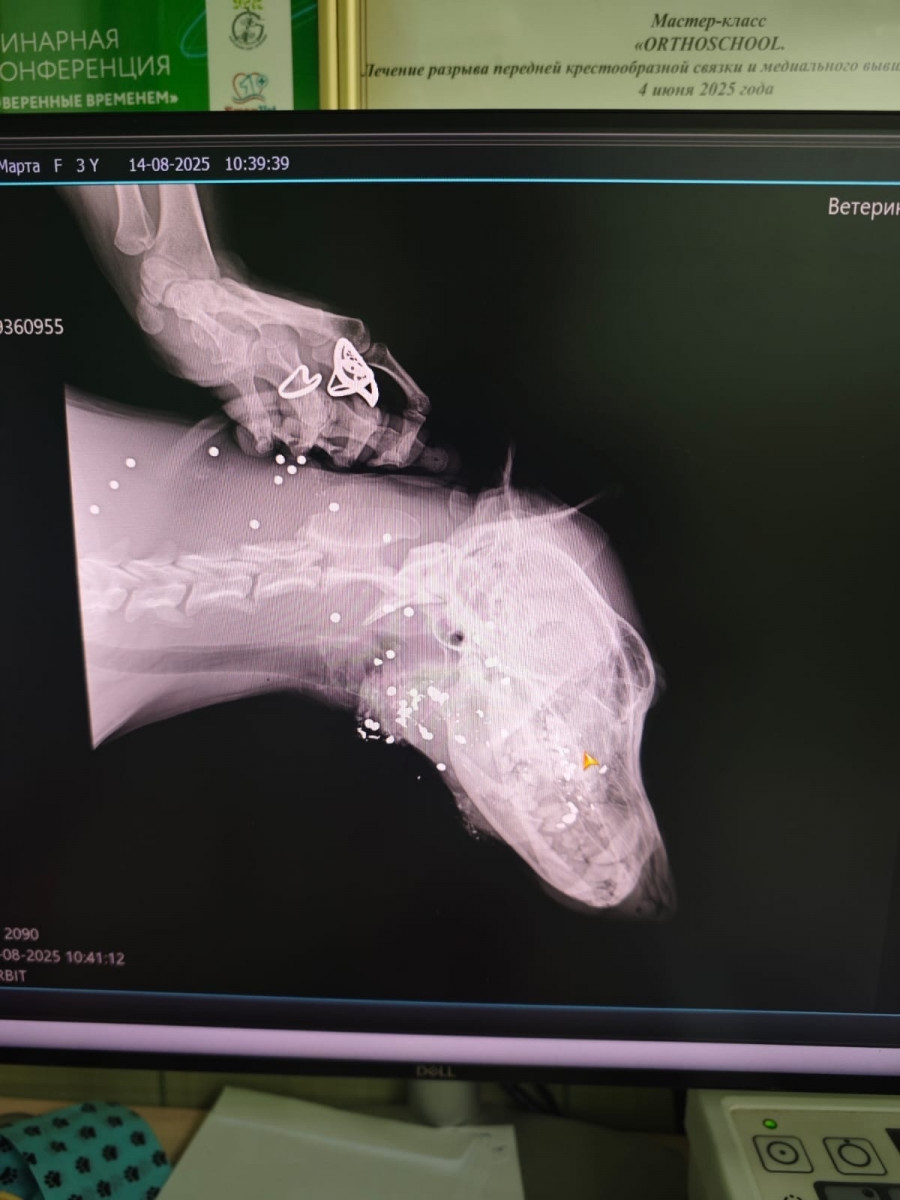

Садоводы СНТ № 9 «Озерки» под Нижним Тагилом обратились в редакцию АН «Между строк» и рассказали о случае жестокого обращения с животным. По их словам, один из их соседей по просьбе председателя садового товарищества решил избавиться от местной бездомной собаки, выстрелив в неё с близкого расстояния, в результате чего животное получило тяжёлые травмы, но выжило. У собаки серьёзно повреждён глаз, его придётся удалить.

Сейчас Марта, так местные назвали собаку, проходит лечение за счёт средств неравнодушных и при помощи волонтёров, ей предстоит долгое восстановление.